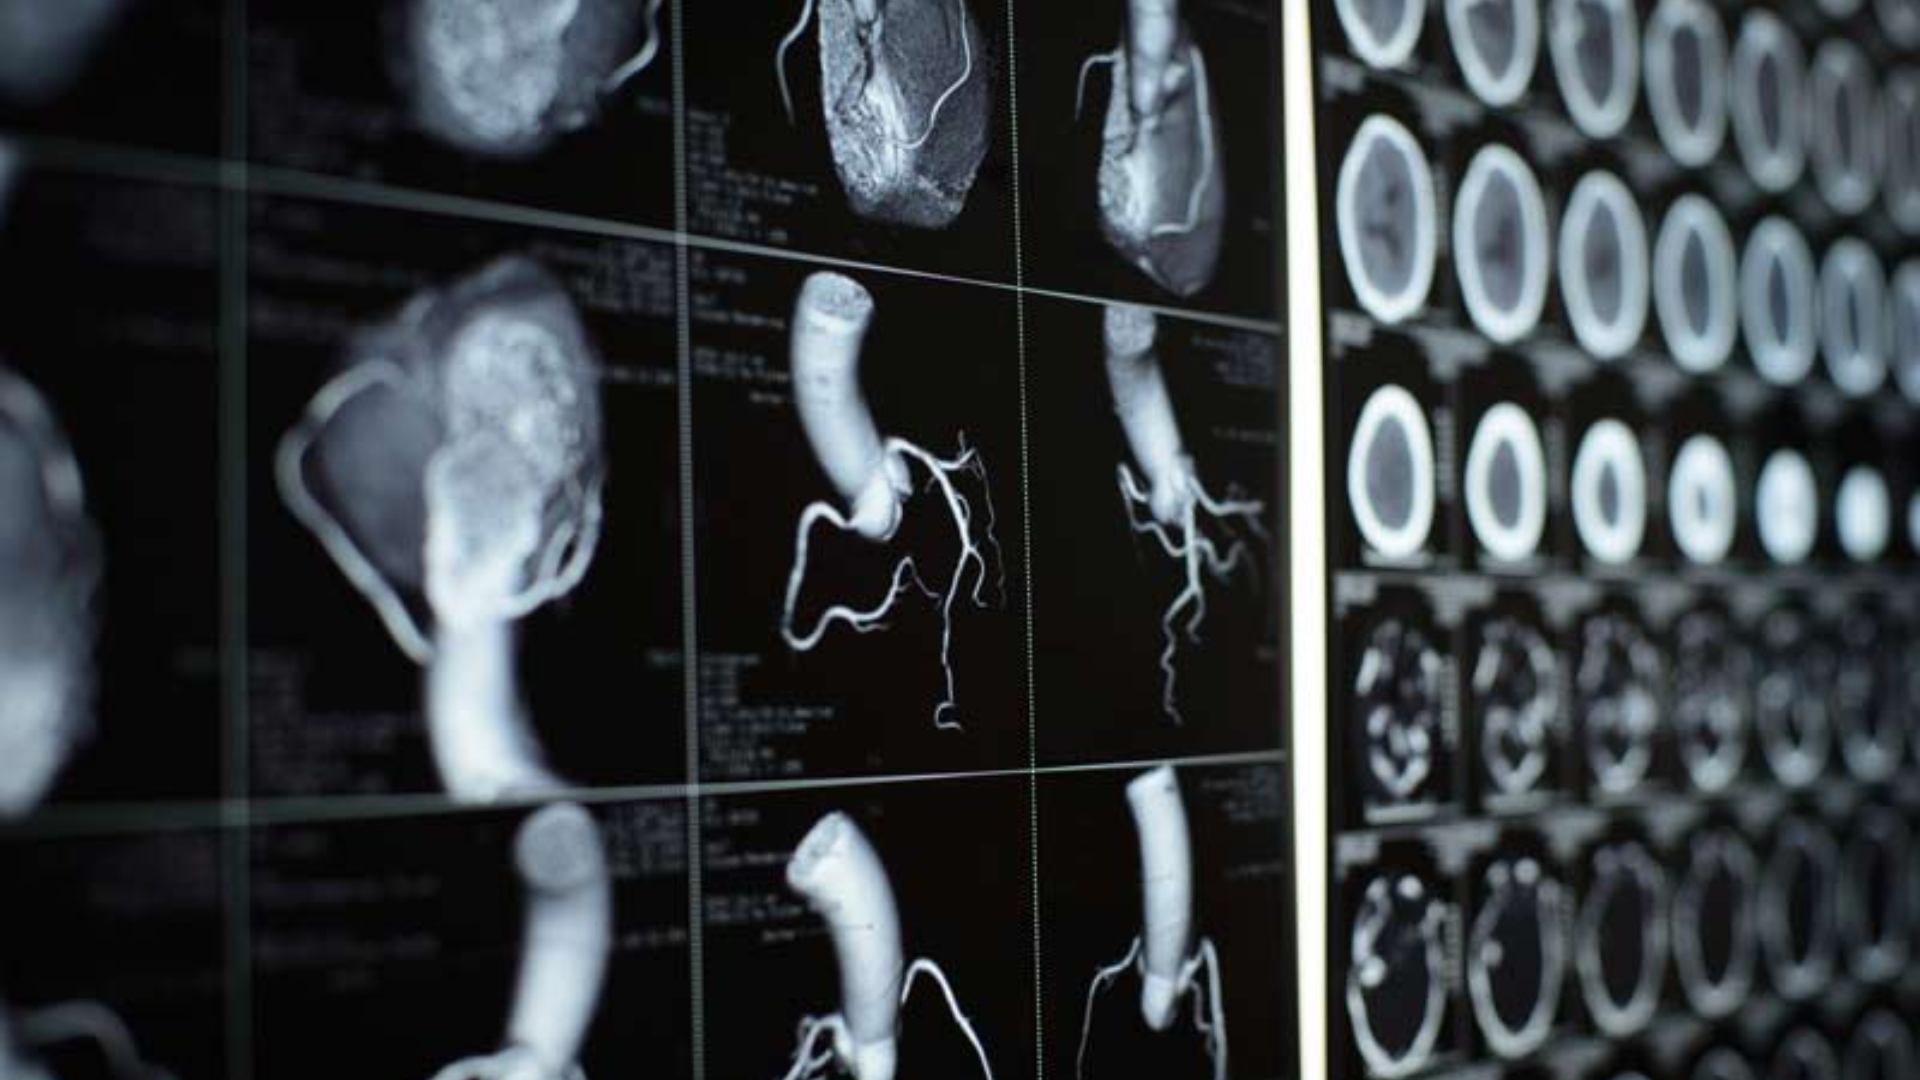

CT tim cho phép tái tạo hình ảnh tim theo nhiều mặt cắt và không gian ba chiều, giúp bác sĩ đánh giá chính xác cấu trúc giải phẫu và phát hiện nhiều bất thường tim mạch. CT tim là khái niệm rộng, trong đó CT mạch vành là một kỹ thuật chuyên sâu thuộc nhóm CT tim.

- Phình động mạch chủ;

- Bóc tách động mạch chủ;

- Dị dạng mạch máu lớn quanh tim.